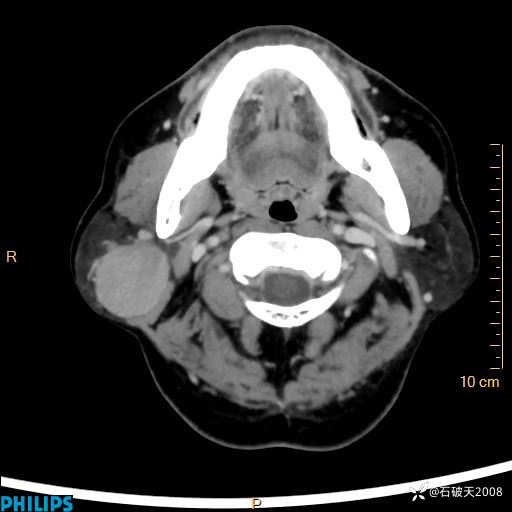

静脉期